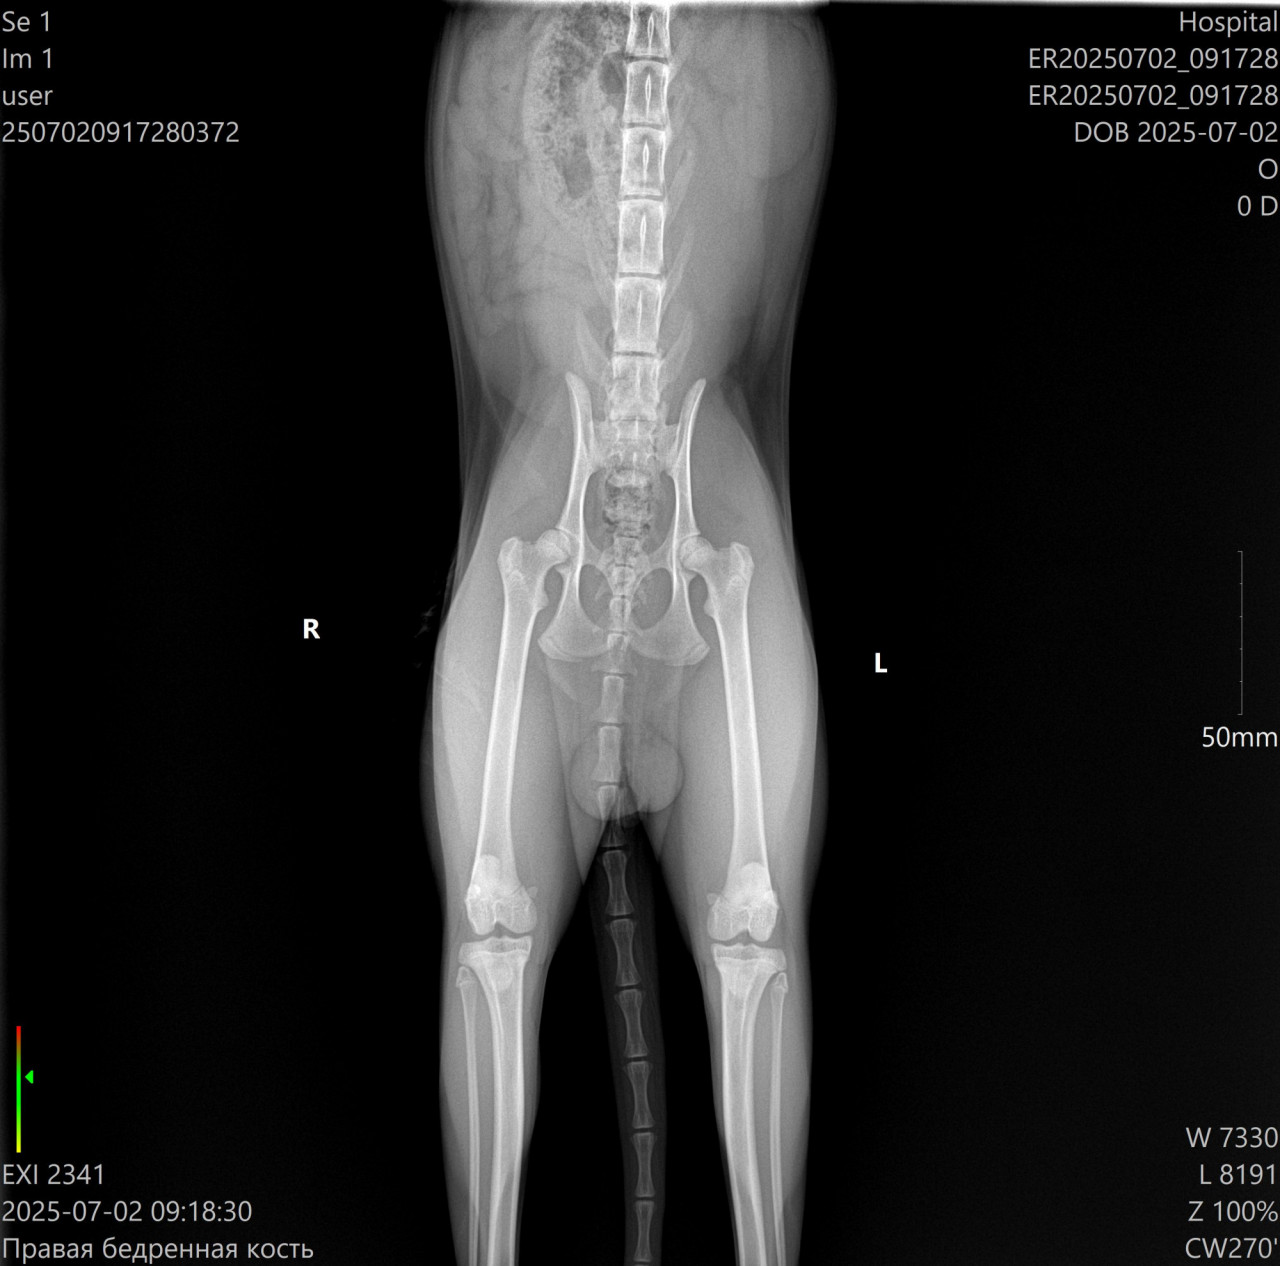

Добрый день! Шотландский вислоухий котенок, возраст 8 месяцев. Активный, играет, бегает. Есть проблема - при ходьбе он заваливается в сторону, то в одну, то в другую. Не всегда, но зачастую. Сам по себе он длинный, лапы высокие, длинный хвост. Возила к ветеринару, сделали снимок таза и задних лапок, сказали всё нормально, всё в пределах нормы. вроде как ему так удобно, он так и ходит... Может ли такое быть, когда кот ходит-шатается-заваливается на бок потому что ему так удобно?

здравствуйте. По снимку явных патологий костей таза и задних конечностей не видно, суставы выглядят без выраженных изменений. Но шаткость при ходьбе может быть связана не только с костями, а и с неврологическими или вестибулярными проблемами. Если симптом сохраняется или усиливается, рекомендую пройти очный осмотр у невролога и ортопеда и возможно сделать рентген в других проекциях или провести неврологическое обследование.

Здравствуйте. По рентгену грубых нарушений костей и суставов не определяется, но подобное поведение не считается нормой. Заваливание на бок может быть связано с нарушением координации, проблемами с нервной системой, вестибулярным аппаратом или скрытой болью. Рекомендую не ограничиваться одним рентгеном и показать котёнка неврологу возможно сделать дополнительные исследования (МРТ, анализы) для исключения патологии.